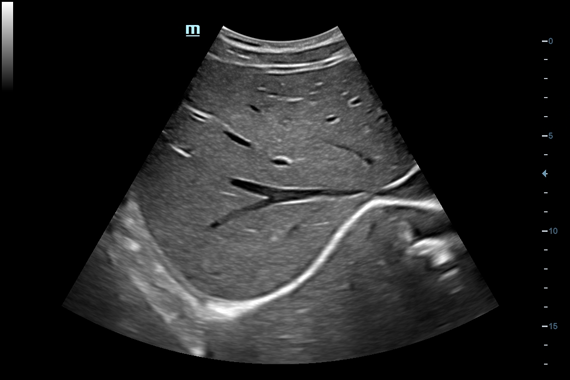

• iScape™ View - панорамное сканирование – отображение на экране объектов большой протяженности (одновременное отображение на экране крупных объемных образований, структур и органов на большом протяжении и т.д.) с возможностью проведения расчетов и измерений.